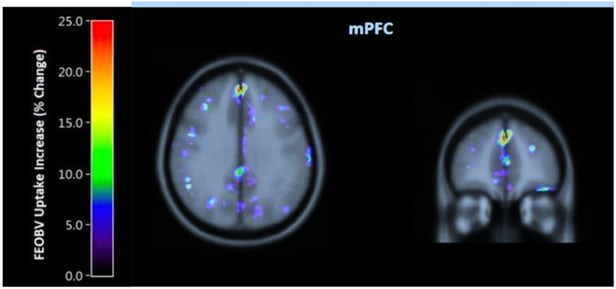

Томографический тест изменений мозга проводился на небольшой группе испытуемых.

Исследование одной из тысяч программ-тренажеров не оценивало скорость и правильность выполнения тестов, а изучало связь интенсивности пользования приложением с синтезом ацетилхолина - нейротрансмиттера, необходимого мозгу для эффективной обработки воспоминаний и обучения. Уровень ацетилхолина в головном мозге уменьшаются с возрастом, а концентрация в мозге пациентов страдающих болезнью Альцгеймера особенно низка. Поэтому когда-то было сделано предположение, что обучение и старческое слабоумие тесно связаны с синтезом этого вещества в головном мозге. И замерив его уровень можно с какой-то долей вероятности говорить что мозг имеет потенциал к обучению и защищен от потери памяти.

Группа подопытных состояла из пяти здоровых, пожилых людей, не страдающих старческим слабоумием. В течение недели они нарабатывали по 12 часов тренировок на программе и ежедневно проходили ПЭТ-сканирование. Анализ показал изменение в четырех областях мозга: правой нижней лобной извилины, левого хвостатого ядра, двусторонней медиальной префронтальной коры и левой языковой извилины / Cuneus. В них выявлено 16-24 процентное возрастание уровня ацетилхолина, что косвенно связали наблюдаемым психологом улучшением внимания.

Небольшая группа ещё не даёт признаваемого результата и полученные данные требуют более полного доказательства эффективности компьютерных тренажеров, но результаты сканирования игроков не намного хуже, чем показывает клиническая практика лечения болезни Альцгеймера. Сейчас в ходу у медиков комплексная терапия ингибиторами холинэстеразы, блокирующими ферменты разрушающие ацетилхолин, а затем пациентам искусственно увеличивают концентрацию нейротрансмиттера в головном мозге. При этом есть некая теоретическая надежда, что такие манипуляции замедляют возникновение дефицита познавательной активности в старческом возрасте.